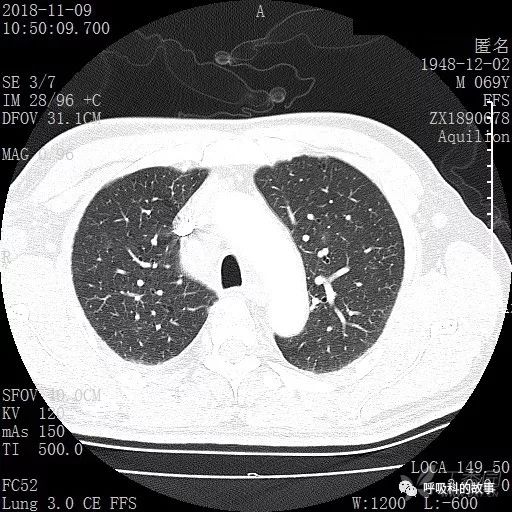

肺窗CT